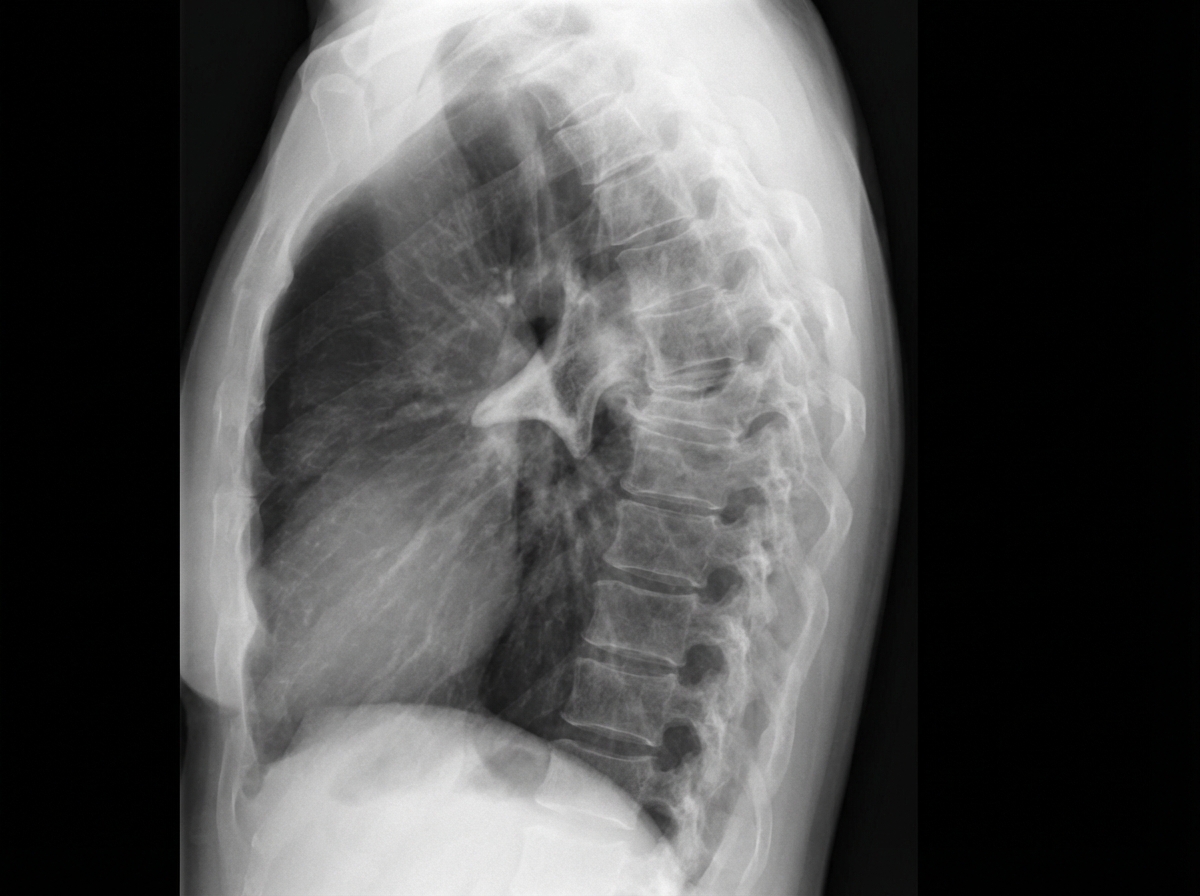

Question 9: Which of the following spine deformities is seen in the image?

- A. Kyphosis

- B. Gibbus (Correct Answer)

- C. Lordosis

- D. Scoliosis

Explanation: ***Gibbus*** - A **gibbus deformity** is a sharply angular posterior projection of a vertebral segment, caused by the collapse of one or more vertebral bodies. - Most commonly due to **Pott's disease (spinal tuberculosis)**, where vertebral body destruction leads to a focal, acute-angle hump. - The image clearly shows a **localized, sharp posterior angulation** in the thoracic spine, which is characteristic of a gibbus. *Kyphosis* - **Kyphosis** refers to an exaggerated **posterior curvature** of the thoracic spine, producing a "rounded back." - While a gibbus is technically a severe form of kyphosis, kyphosis alone describes a more **generalized, smooth curve** — not the focal, angular hump seen in the image. *Lordosis* - **Lordosis** describes an **anterior (forward) curvature** of the lumbar spine, often called "swayback." - This is not seen in the image, which displays a prominent **posterior** projection, not an anterior one. *Scoliosis* - **Scoliosis** is a **lateral (side-to-side) curvature** of the spine, seen as a deviation when viewed from behind. - The image shows a deformity in the **sagittal plane** (anterior-posterior), not the coronal plane, ruling out scoliosis.